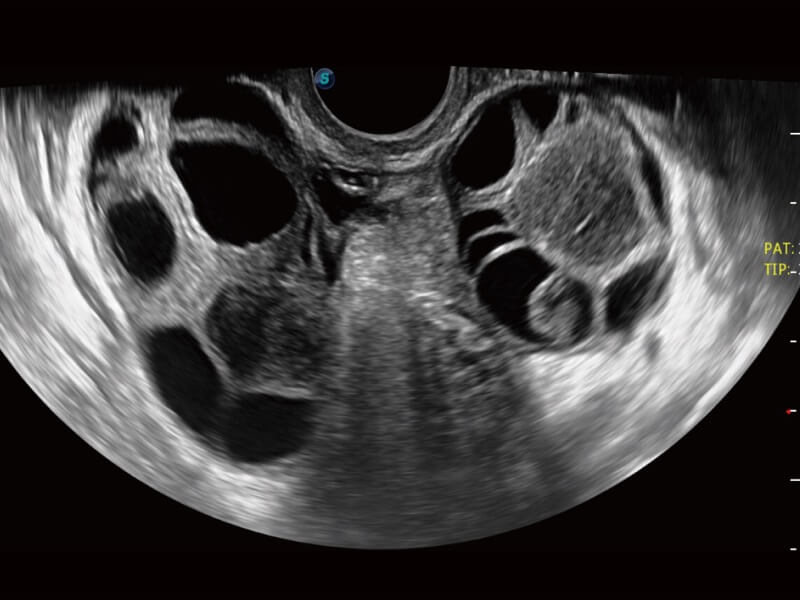

AVC Follicle ermöglicht eine hohe Effizienz bei der Follikelanalyse. Es handelt sich um eine volumenbasierte automatische Berechnung der Anzahl und des Volumens der Follikel. Die Follikel werden in den Ergebnissen nach Größe sortiert und in verschiedenen Farben dargestellt, um die Visualisierung zu verbessern.

Ultraschall wird immer vielseitiger und übernimmt immer mehr klinische Aufgaben. Als Vorreiter, der Ärzten dabei hilft, mehr zu erreichen, ist ELITE mit einer umfassenden Palette fortschrittlicher Funktionen für die Allgemeine Bildgebung, Gynäkologie/Geburtshilfe, Kardiologie und mehr integriert.

Ultraschall wird immer vielseitiger und übernimmt immer mehr klinische Aufgaben. Als Vorreiter hilft ELITE den Ärzten dabei, mehr zu erreichen, indem es mit einer umfassenden Palette fortschrittlicher Funktionen ausgestattet ist, die die allgemeine Bildgebung, die Geburtshilfe/Gynäkologie, die Kardiologie und vieles mehr abdecken.